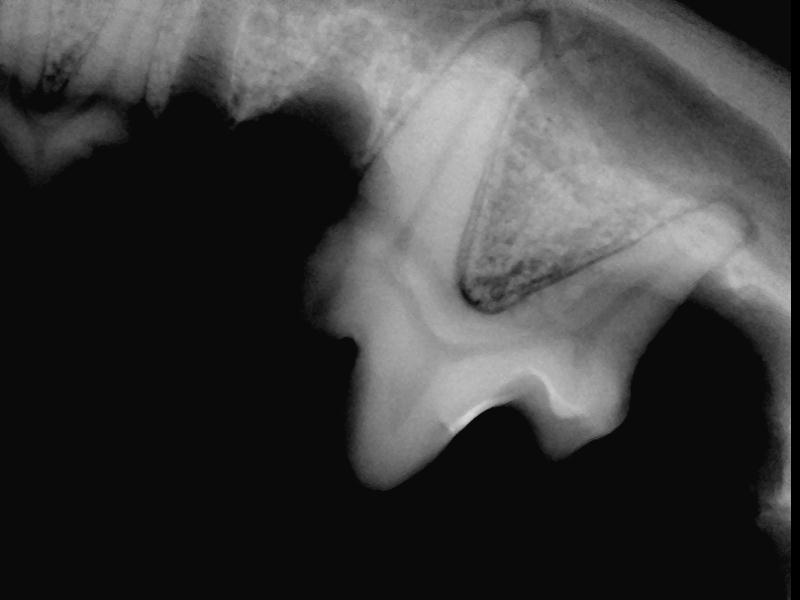

Tandrøntgen er et uundværligt hjælpemiddel i daglig dyrlægepraksis.

Via tandrøntgen ses eventuelle rod problemer, som ikke ville være opdaget ved blot at se på selve tanden.